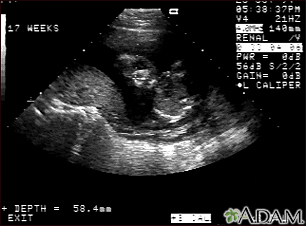

Ultrasound, normal fetus - face

This is a normal ultrasound of the fetus performed at 17 weeks gestation. The fetal face can be seen in the middle of the screen. The head is tilted left toward the placenta, which can be seen as a mound in the left of the ultrasound image. Both eyes are visible, and the area of white within the eye is the lens. Other facial features, such as the nose and mouth, are also visible.